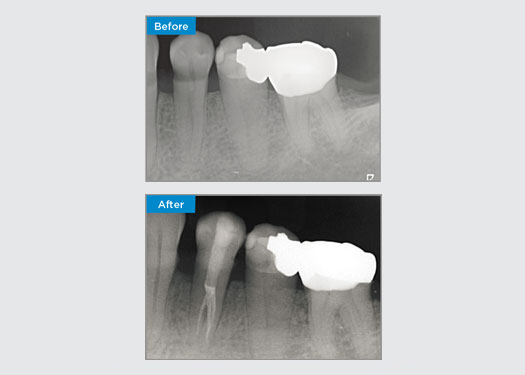

Een 35-jarige vrouwelijke patiënt presenteerde zich na verwijzing door een specialist-parodontist. Tijdens de initiële endodontische beoordeling zei de patiënt dat kroonverlenging was uitgevoerd, voorafgaand aan het plaatsen van de kroon op tand 16, twee jaar eerder. Twee maanden voordat patiënte zich presenteerde, had zij zwelling van de palatale gingiva opgemerkt. De algemene tandarts van de patiënt had een parodontale pocket van 7 mm ontdekt naast het palatinale sinuskanaal dat hoort bij tand 16. De patiënt werd doorverwezen naar een gespecialiseerde parodontoloog. De gespecialiseerde parodontoloog diagnosticeerde een primaire endodontische - secundaire parodontale laesie. De patiënt had een bevredigende mondhygiëne en was een regelmatige tandartsbezoeker. Tand 16 was gevoelig voor percussie. Er werd opgemerkt dat de kroonranden bevredigend waren en dat de parodontale pockets rond tand 16 minder dan 2 mm diep waren aan de buccale kant, maar op het palatale oppervlak, grenzend aan het sinuskanaal, was er een geïsoleerde parodontale pocket van 6,5 mm. Thermische tests van tand 16 toonden een negatieve respons. Tand 16 had risicofactoren voor apicale parodontitis zoals: een negatieve reactie op thermische testen, gevoeligheid voor percussie, een voorgeschiedenis van een diepe restauratie na een kroonverlengende operatie en radiografisch identificeerbare periapicale ziekte. Tand 16 had geen voorgeschiedenis van pijn bij bijten of kauwen, wat kan duiden op een scheur die communiceert met de pulpa en/of parodontale weefsels. De patiënt had geen risicofactoren voor parodontitis en er waren geen abnormaal diepe pockets rond andere tanden.

Dr. Omar Ikram, endodontist, Crows Nest, NSW Australië